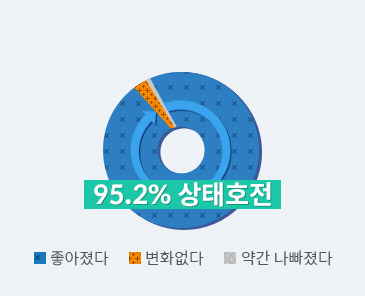

척추관협착증 한방통합치료 만족도 - 3년 후에도 환자의 약 90%가 만족

치료 3년 뒤 호전도

치료 3년 뒤 만족도